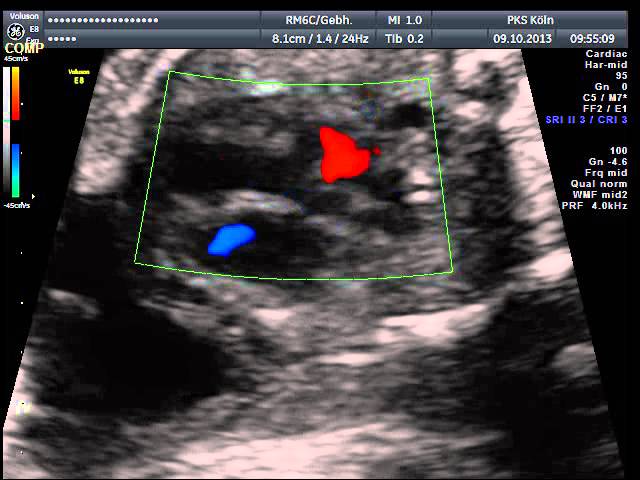

Das Entdecken und die Beurteilung von fetalen Herzfehlern erfordert ein hohes Maß an Untersuchungserfahrung und eine entsprechende Geräteausstattung, sodass sie häufig im Rahmen von Routineuntersuchungen nicht erkannt werden. Daher sollten gerade Eltern mit einem erhöhten Risiko für fetale Herzfehler diese Untersuchung des kindlichen Herzens durchführen lassen.

Alle Untersuchungen werden an High-end-Geräten durchgeführt, die technisch auf dem allerneuesten Stand sind. Diese Untersuchung kann bei entsprechender Indikation mit Überweisung vom betreuenden Frauenarzt erfolgen oder als Wunschleistung ohne Indikation.